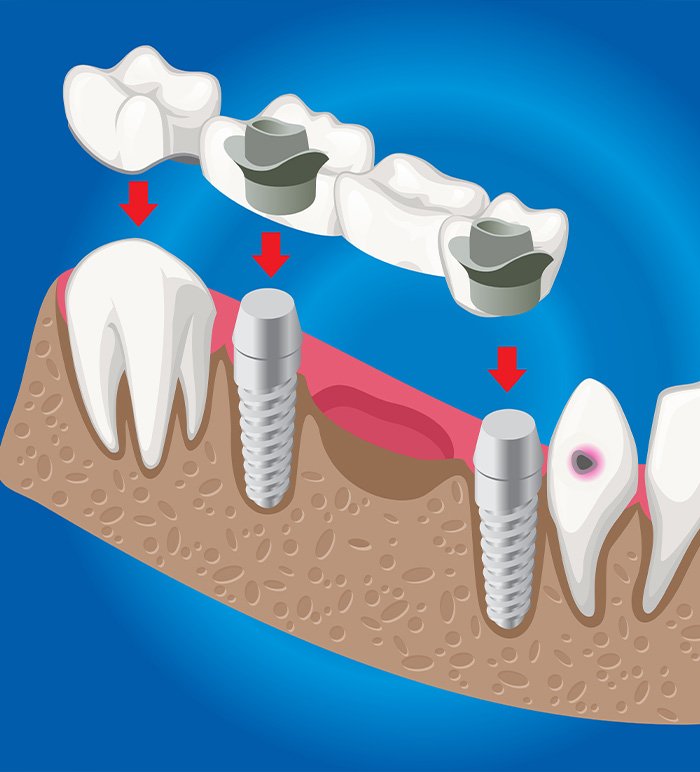

Diş Köprüleri, eksik bir veya birden fazla dişi yerine koymak için kullanılan sabit bir diş tedavi yöntemidir. Diş Köprüleri, boşlukları doldurmak amacıyla, komşu dişler üzerine yerleştirilen köprüler ile eksik dişin yerini alır. Genellikle iki komşu dişe (bu dişler “yatak dişi” olarak adlandırılır) bağlanan ve boşluğu kapatan bir veya daha fazla yapay dişten oluşur.

Diş Köprüleri, hem estetik hem de fonksiyonel açıdan doğal dişlerinizi taklit eder ve eksik dişin neden olduğu çiğneme, konuşma gibi sorunları çözmeye yardımcı olur. Uygulama süreci, dişlerin hazırlanması ve köprünün yerleştirilmesiyle tamamlanır. Diş köprüleri, genellikle porselen, metal ya da her ikisinin kombinasyonundan yapılan sağlam ve uzun ömürlü bir çözüm sunar.

Diş Köprüleri Nasıl Uygulanır?

Diş Köprüleri uygulaması, genellikle eksik dişlerin yerine bir veya daha fazla dişi tamamlamak için yapılan bir tedavi yöntemidir. Uygulama süreci genellikle birkaç aşamadan oluşur. İlk olarak, diş hekimi, köprü uygulanacak alanı değerlendirir ve komşu dişlerden bir veya birkaçını, köprünün desteklemesi için küçültür. Bu işlem, dişlerin üzerine porselen veya metal bir kaplama yapılabilmesi için gereklidir.

Ardından, bu şekillendirilen dişler üzerine geçici bir köprü yerleştirilir. İkinci aşamada, ağızdan ölçü alınarak, kalıcı köprü için kişiye özel bir model oluşturulur. Diş hekimi, dişlerinize uyumlu ve estetik açıdan hoş bir köprü tasarımını bu model üzerinde hazırlar. Üçüncü aşamada, kalıcı köprü yerleştirilir ve düzgün bir şekilde oturması sağlanır. Uygulama sonrasında, diş hekiminiz, köprünün düzgün oturduğunu ve doğru bir şekilde işlev göreceğini kontrol eder.